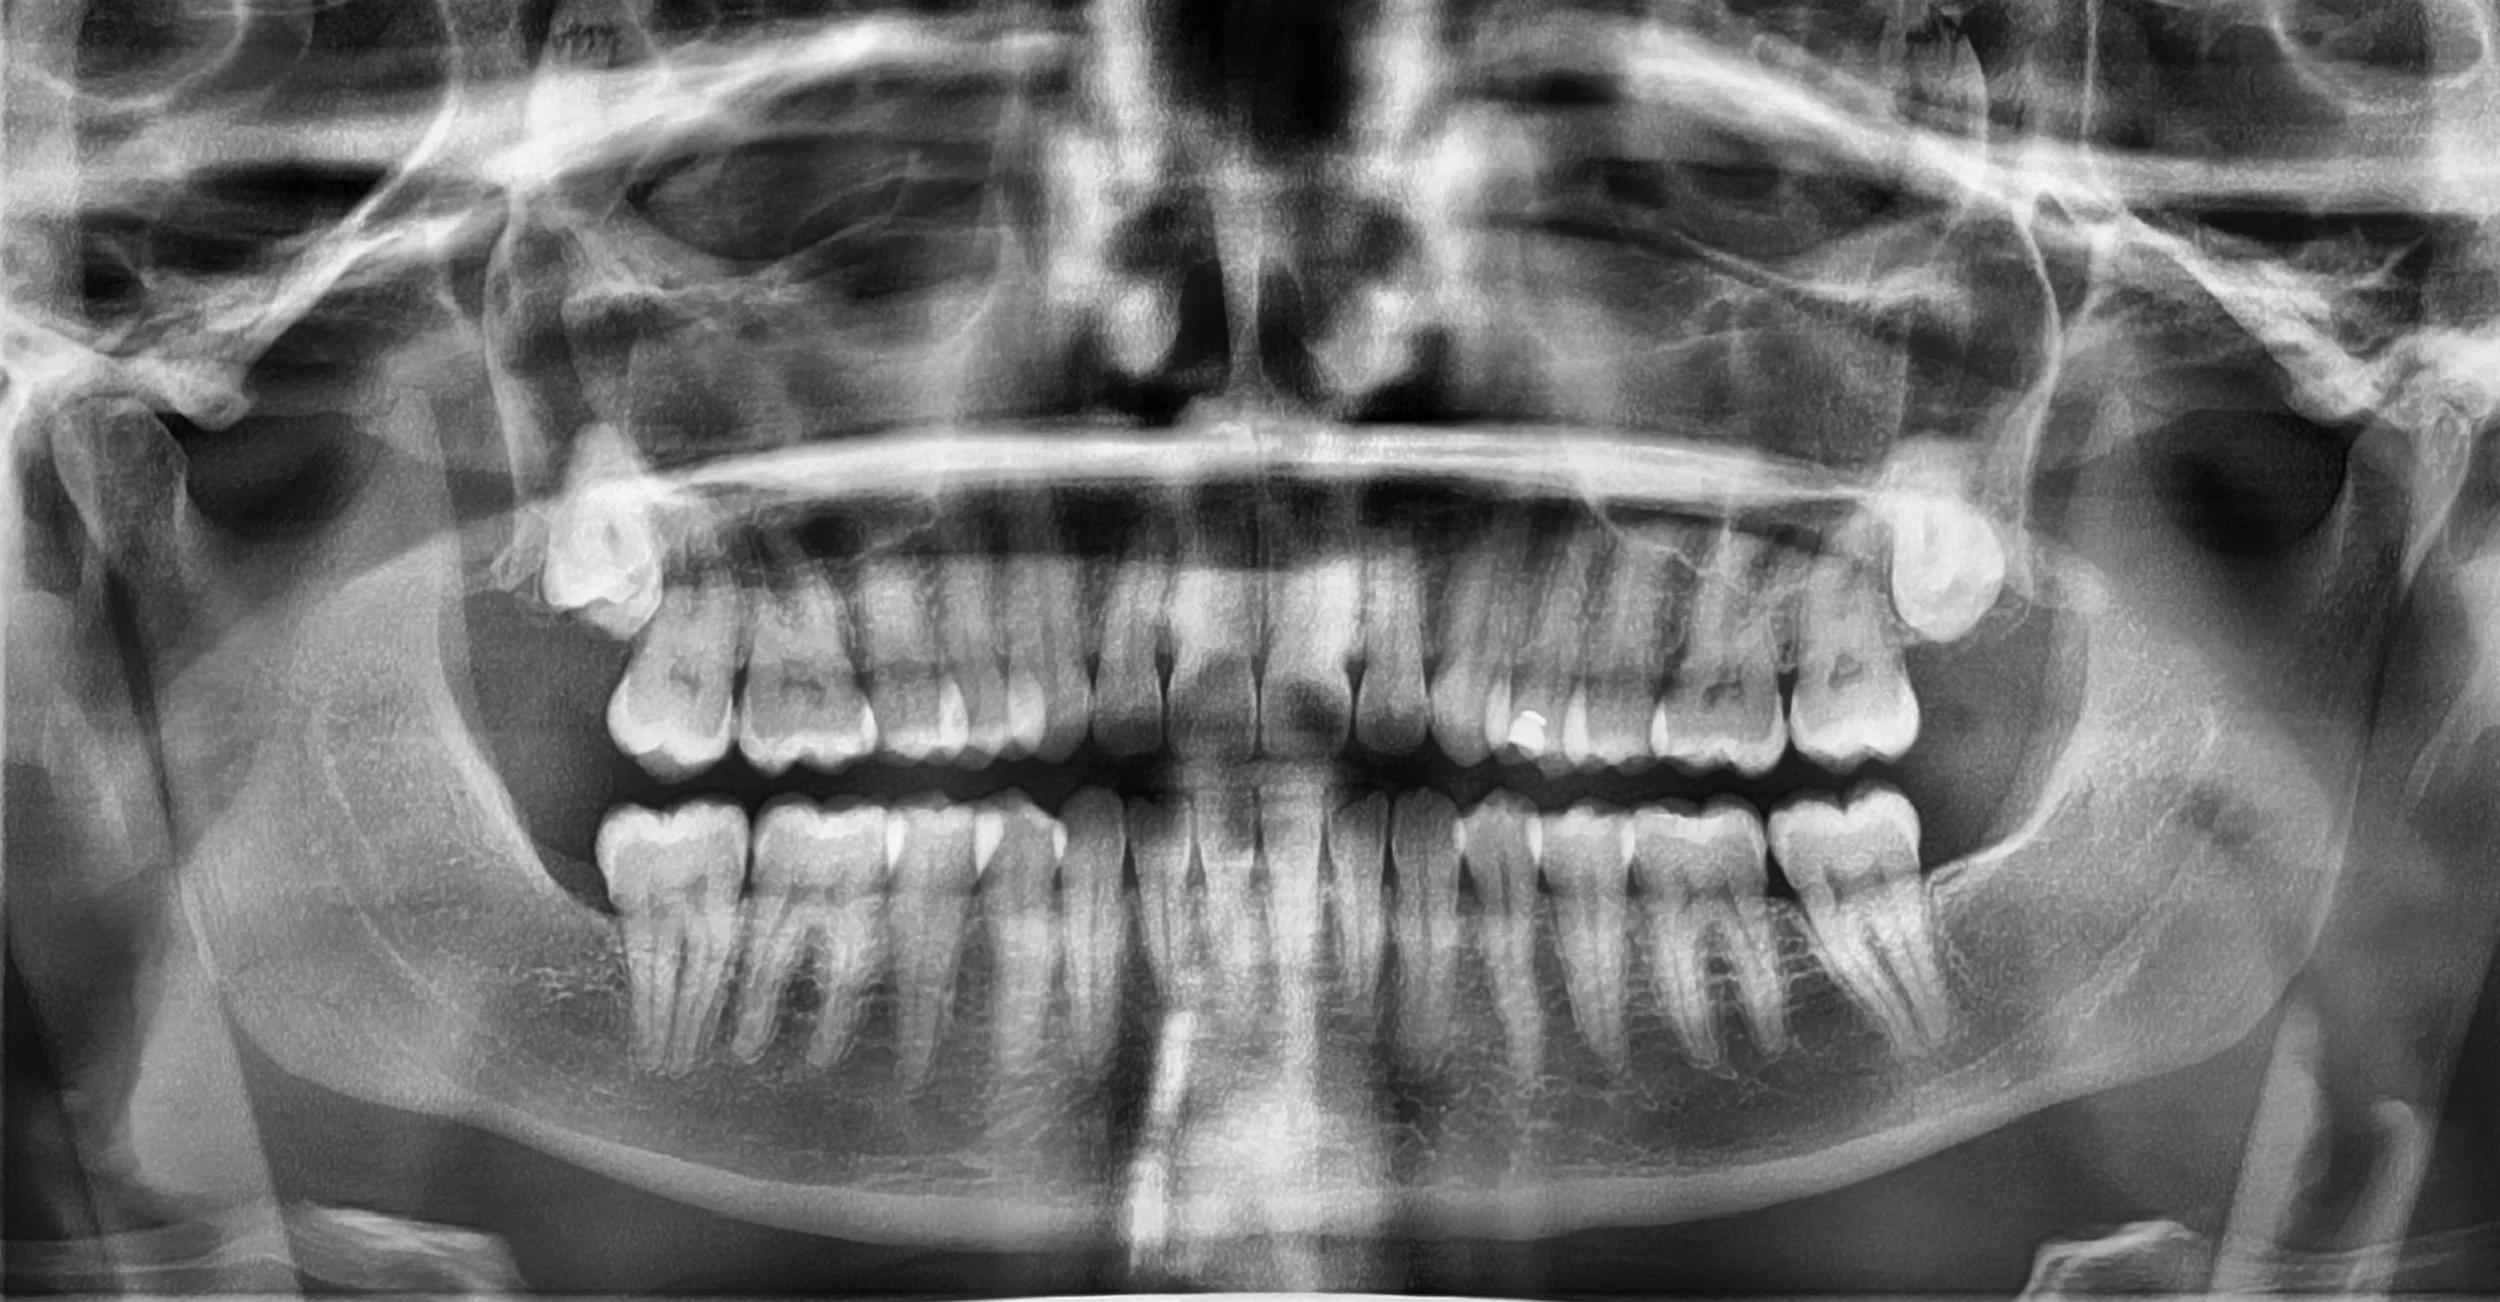

A full OPG radiograph of your mouth

Digital X‑rays pop up on the screen instantly, which means your dentists can walk you through what they’re seeing in real time. It’s a simple, quick way to get a baseline of what’s happening under the surface. With the latest in technology, we can create images that give small detailed insights to localised areas or larger OPGs creating full mouth images. We’ve also fortunately got special cephalometric radiographs that will aid in planning for orthodontics. This isn’t something that is widely available but our specialist orthodontists will love us for - more about that later….